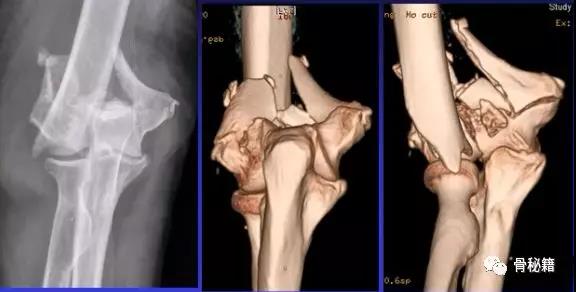

详细的术前评估

X线、CT、神经、等等